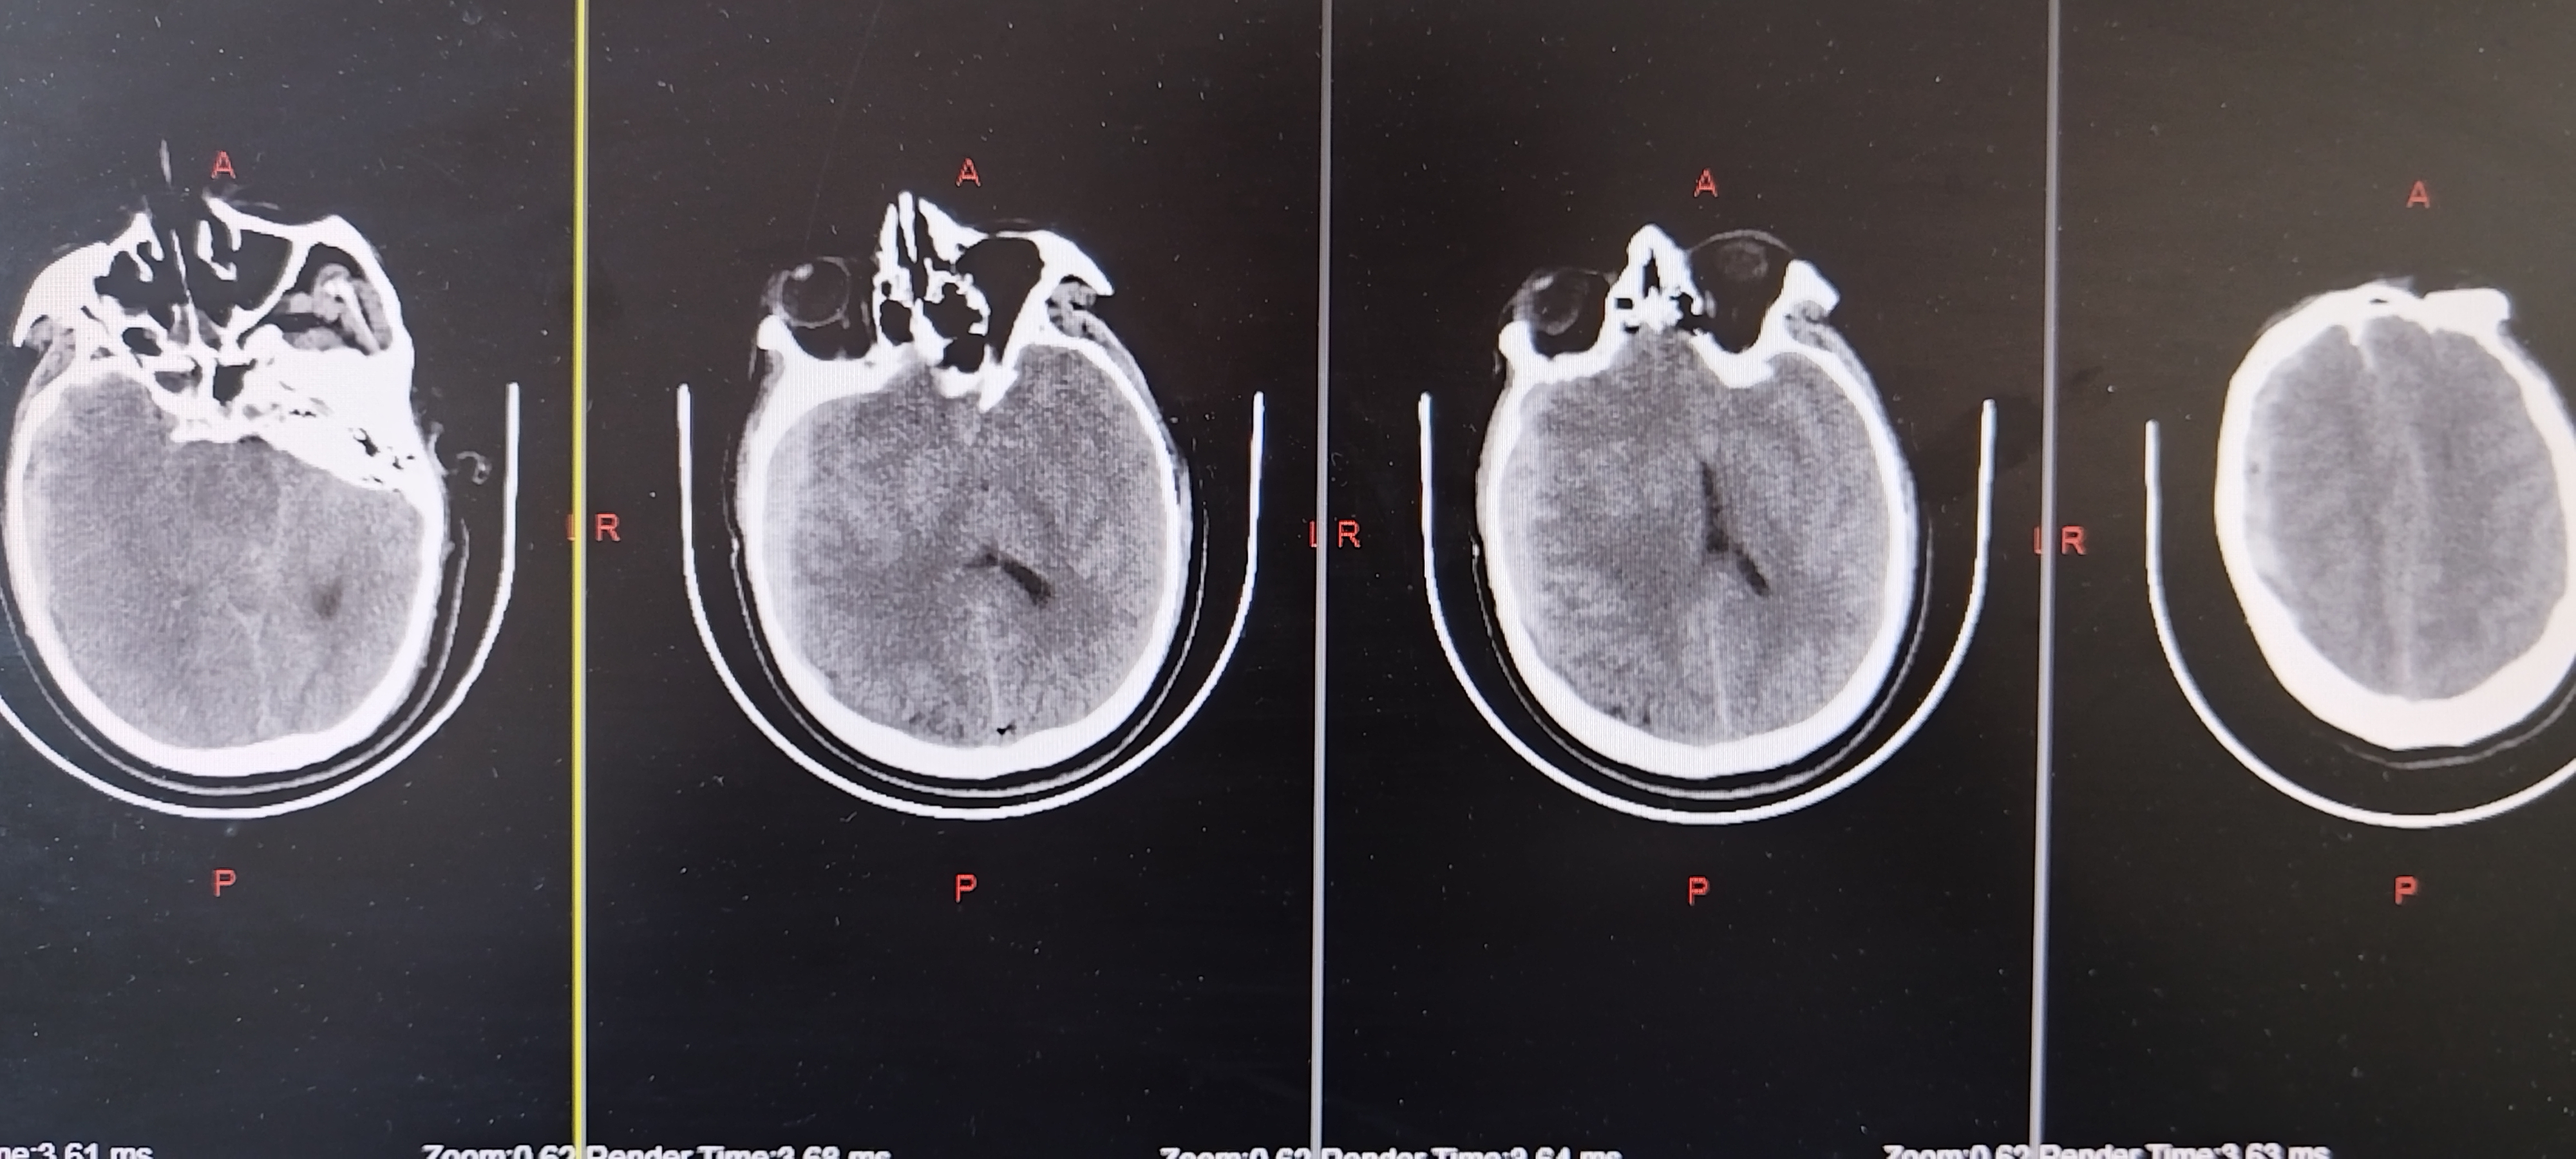

头部外伤后意识不清约1.5小时入院。既往体健。患者1.5小时前不慎摔倒致头部受伤,当即意识不清,急诊查头颅CT显示右侧额颞顶硬膜下血肿,蛛网膜下腔出血,左侧后颅凹骨折,中线移位,脑疝可能。查体:深昏迷,E1V1M1,双侧瞳孔不等大左:右约4.0mm:1.5mm,对光反射消失,口含口咽通气道,四肢肌张力不高,生理反射减退,双侧病理征(+)。

术后1天复查CT